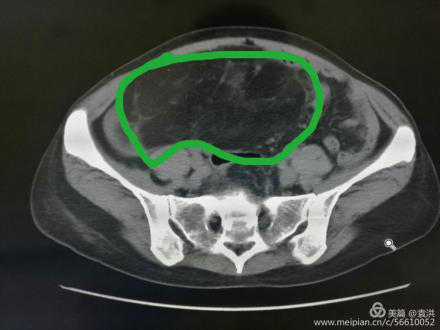

這一檢查讓婦科醫(yī)生也大吃一驚!醫(yī)生檢查時(shí)觸及腹部一硬質(zhì)包塊,無(wú)明顯邊界,上至劍突下,下至盆腔,兩側(cè)至腋中線,無(wú)壓痛,固定,說(shuō)明這包塊占據(jù)了患者整個(gè)腹腔,考慮來(lái)源于其它臟器,立即行全腹CT檢查??苫颊哂忻荛]空間綜合癥,一開(kāi)始拒絕CT檢查,醫(yī)生反復(fù)給患者做思想工作,并強(qiáng)調(diào)此項(xiàng)檢查的重要性,患者足足猶豫了兩天,才終于在醫(yī)護(hù)人員及家屬的鼓勵(lì)下順利完成了檢查。腹部CT提示,高度懷疑右腎有一顆脂肪肉瘤。

遂請(qǐng)泌尿外科會(huì)診協(xié)助診治,經(jīng)檢查,結(jié)合CT考慮腎周?chē)蚋鼓ず竽[瘤。最終診斷為:右腎巨大脂肪肉瘤。且腫瘤從腹腔延至盆腔,腹腔臟器受壓推移。醫(yī)生建議,子宮肌瘤多為良性,不影響生命,可暫緩手術(shù),但右腎巨大脂肪肉瘤必須盡快手術(shù)摘除。